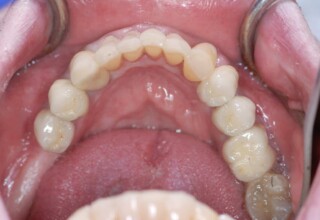

Full mouth prosthetic reconstruction on implants with a different approach on upper and lower jaw

Lower jaw: extractions, direct implant placement and immediate loading (same day) with a transitional bridge.

Upper jaw: Sequential extractions, sequential implant placement and gradual incorporation in the temporary bridge so that the patient was never left without fixed teeth. The aim of the above approach was to have the patient in continuous functional and aesthetic reconstruction, without immediate loading due to anatomical restrictions. Old smiling photos of the patient were used because the natural shape of the teeth was completely lost due to repetitive prosthetic attempts. Tooth relationship and teeth-lip support was transferred to the temporary restorations. Two different transitional bridges were needed to fully estimate phonetics, mastication and esthetics. After the necessary adjustments were finalized, the temporary bridge was used as a guide for the permanent bridges.

Initial

Intermediate

Final